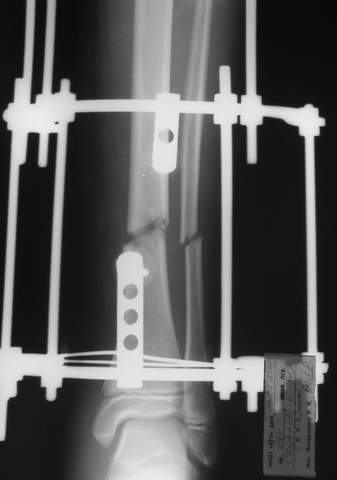

АВФ -отдельная история в нашем краю, поэтому последний вариант -открытая репозиция, что я и сделал: Без мобилизации отломков б.б. репозиция м.б. не получалась. Первым делом фиксировал перелом м.б. кости пластиной на 4 4,5 мм винтах,

при ревизии зоны перелома б.б. кости сохранялось смещение дистального отломка кпереди, пришлось принять меры и решить эту проблему.

Помятуя наш недавний разговор о фиксации м.б. кост, высылаю послеоперационные картинки..

Напомню- разбирали случай 17 летнего молодого человека перелом дист тиб.фиб. хирургия после 3 недель с момента травмы( безуспешные попытки закрытой репозиции) Раны заживают первичным натяжением, занимается физиотерапией, пока никаких проблем не наблюдается